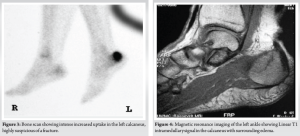

The calcaneus is one of seven tarsal bones and is part of the hindfoot, which includes the calcaneus and the talus [1]. Stress fractures are relatively uncommon injuries, accounting for approximately 1–7% of all athletic injuries, occurring as a result of overuse [2,3]. They occur over time as a result of repetitive forces causing microscopic damage to the bone, as well as in cases where physical activity is increased in the setting of relative energy deficiency [4]. The signs and symptoms of stress fractures may include: Slowly developing generalized pain in the heel area, swelling in the heel area, as well as a positive calcaneal compression test [4]. The diagnostic capability of X-rays is limited, as stress fractures may only appear on X-ray once the fracture has started to heal (after 2–3 weeks of symptoms), at which point a sclerotic or radiolucent line may be visible. With more advanced imaging, a stress fracture will appear darker on the bone scan than an uninjured area. With this type of injury, this would be visualized on MRI as a line in the trabecular calcaneus, hypo-intense in all sequences, surrounded by an area of abnormal bone marrow signal due to local edema (hypo-intense on T1-weighted and hyper-intense on fluid-sensitive images) [5-7] (Fig. 2-4).